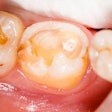

Canary System now integrates with practice management software